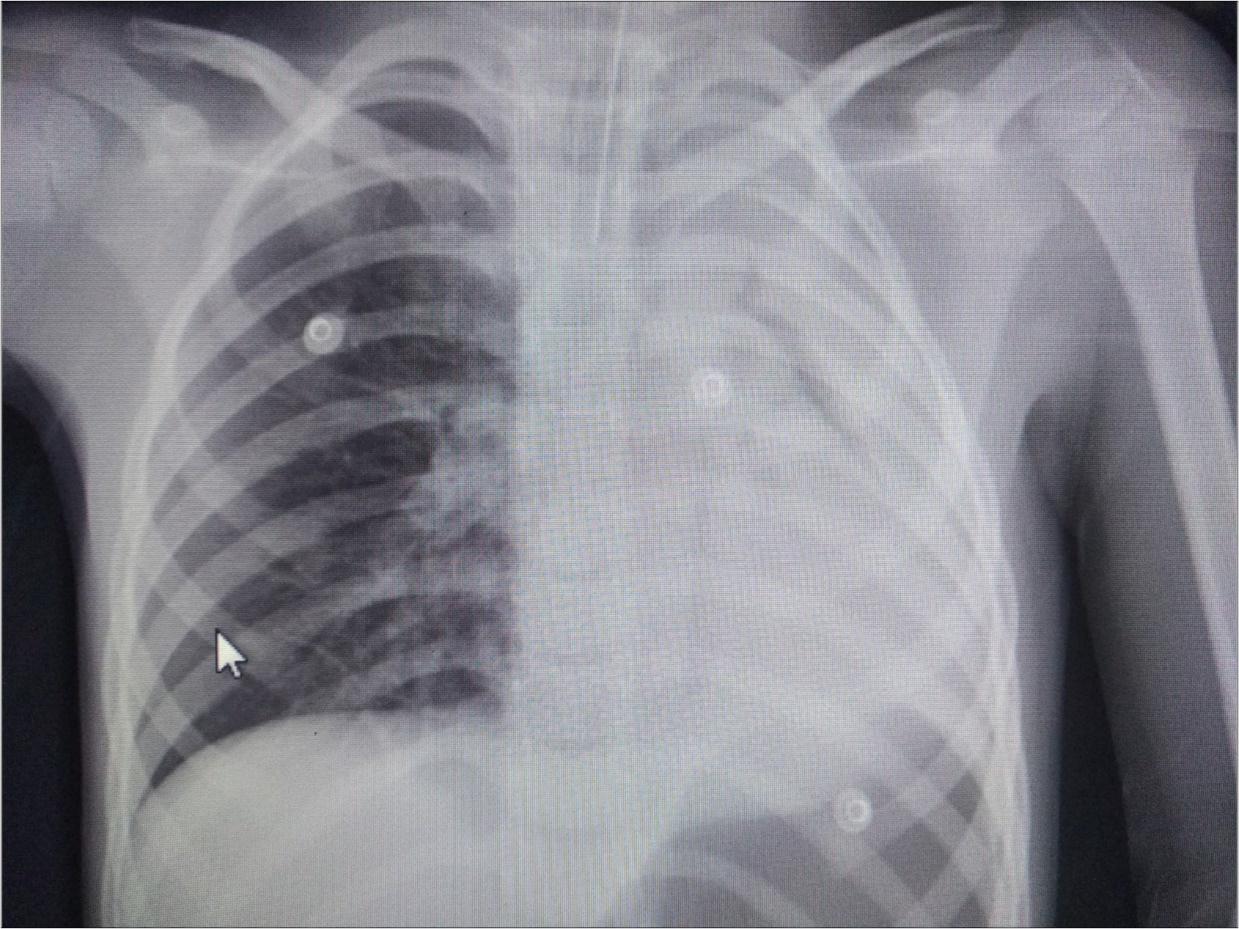

A 6 year-old boy was admitted to our hospital with the symptoms of upper respiratory tract infection (URI). He had hemoptysis 2 days prior to admission to hospital. On admission he had respiratory distress, fever (39°). Plain chest graphy demonstrated a complete opacification of the left lung (Figure 1). Thorax ultrasonography was normal and high resolution computed tomography (HRCT) of the chest revealed a 50-60% narrowing of the left main stem bronchus starting from carina downwards (Figure 2). Although there was no history of foreign object aspiration an emergent bronchoscopy was performed for a possible unnoticed aspirated foreign body. A bronchial cast located at the carineal bifurcation of trachea measuring 3x1 cm was detected and easily removed with forceps during bronchoscopy (Figure 3). The material was whitish, rubbery in consistency. Histopathologic examination of the cast revealed that it consisted of condensed fibrin, neutrophils and eosinophils. Culture was also obtained from the specimen for a possible bacterial growth. Following bronchoscopy the patient required mechanical ventilation for ventilatory support in the mode of high frequency oscillatory ventilation (HFOV) with supplementery oxygen in intensive care unit (ICU). In his 3rd hospital day, control chest graphy of the child showed complete opacification of the left lung and for a chance of residual cast in the tracheobroncial tree a repeat bronchoscopy was performed. Two seperate casts from the left main stem bronchus measuring 1.5x1 cm and 2x1 cm in length were removed with forceps and lavage with aspiration of both right and left main stem bronchus was performed. Following second bronchoscopy the transcutaneous oxygen saturation increased from 77 to 99 and control chest roentgenogram showed equal expension of both lungs. While in his stay in ICU, in addition to mediacal treatment, respiratory physiotherapy was performed regularly. He was medically treated with aerosolized dexamethasone with adrenalin. Bacterial test obtained from cast was found positive for Streptococcus viridans and vancomycin was started. On his 5th day in ICU, his respiratory status worsened and a chest graphy showed a decrease in expension of the left lung and a control bronchoscopy was performed. In this third bronchoscopy trachea and both right and left main stem bronchus were found to be patent but were found to have excessive viscous secretions. Pulmonary toilet including lavage and aspiration of thick tenacious secretions was performed. On day 12 he was transferred from the ICU and 1 week later he was weaned off the ventilator. He underwent pulmonary rehabilitation. During his 3rd year of follow up he has no further episodes of respiratory distress and he is disease free.

Figure 1.Chest radiograph showing left-sided opacification.

Chest radiograph showing left-sided opacification.

Radiographic findings are nonspecific and include atelectasis secondary to airway obstruction, hyperinflation due to air trapping, unilateral opacification, as seen in our case, bronchiectasis and lung infiltrates. It has been reported that HRCT may allow in some cases the visualization of bronchial casts in the airways of larger caliber 19. However the gold standard in diagnosing PB is bronchoscopy which reveals the airway obstruction by BC 3.